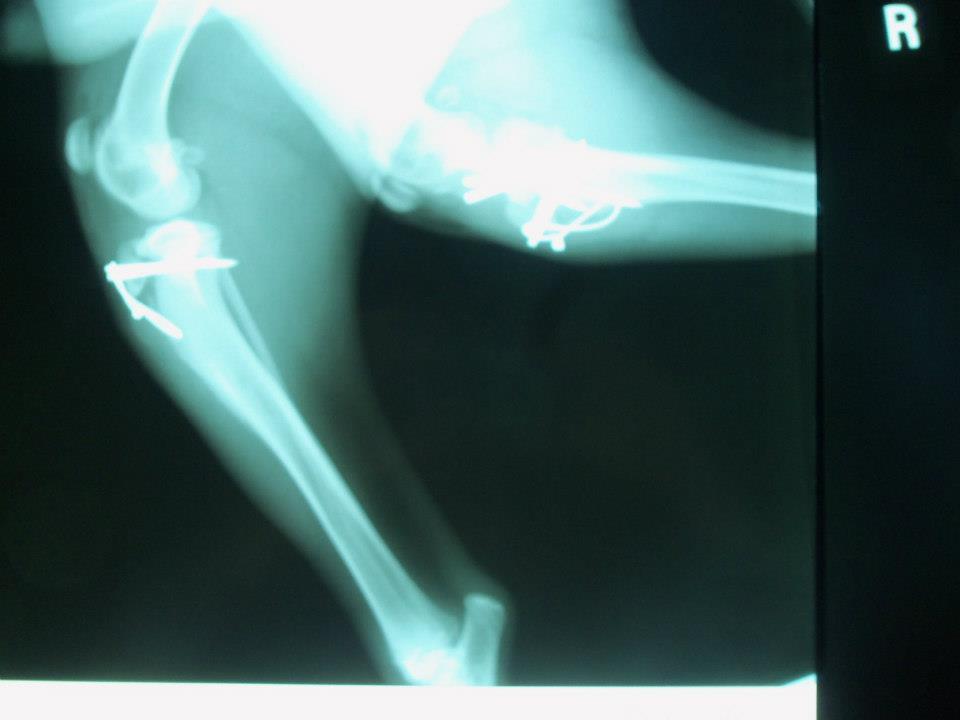

Once they were happy with how it looked in there, they had to put my legs back together Luckly they didn't lose any parts  :D

Look at all that hardware in there!  I had to stay calm and still for many weeks which is really hard for a happy bouncy boy like me!

But I'd be able to walk again real soon...